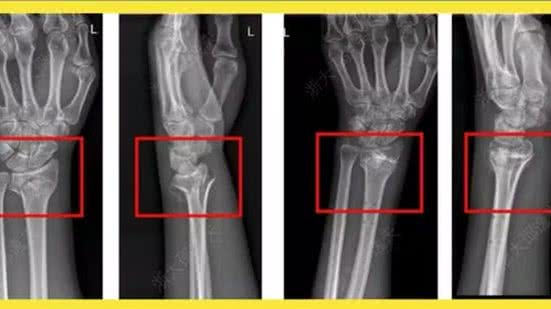

Em caso experimental, um paciente com fratura no punho recebeu uma injeção através de uma incisão de apenas 3 cm e foi curado em apenas três minutos, informou o "Cho Sun Daily". Uma cirurgia para reparar o punho exigiria uma placa metálica e parafusos, cuja remoção exigiria uma segunda cirurgia no ano seguinte. Após um check-up de acompanhamento de três meses, a fratura do paciente havia cicatrizado completamente sem complicações, afirmou a reportagem. Durante os testes, outros 149 pacientes foram tratados com a supercola chinesa, com resultados positivos. O produto já foi patenteado dentro e fora da China.